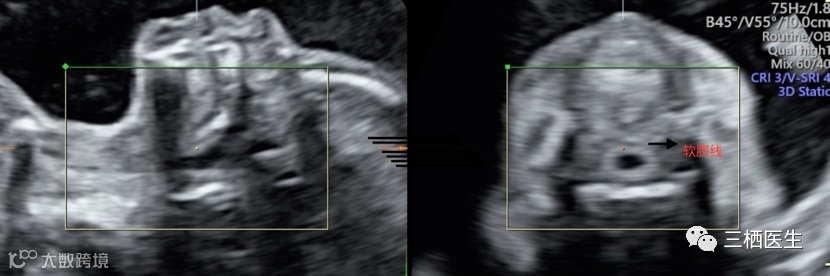

2.软腭线(如果软腭是好的,前面的硬腭也是好的)

完整的软腭线

3.软腭如果异常,再往前看硬腭线,由此确定单纯腭裂的程度。

完整的硬腭线

下图可见硬腭线回声中断:

上述几个切面,最容易扫描的是硬腭线,常常作为筛查严重单纯腭裂的平面。